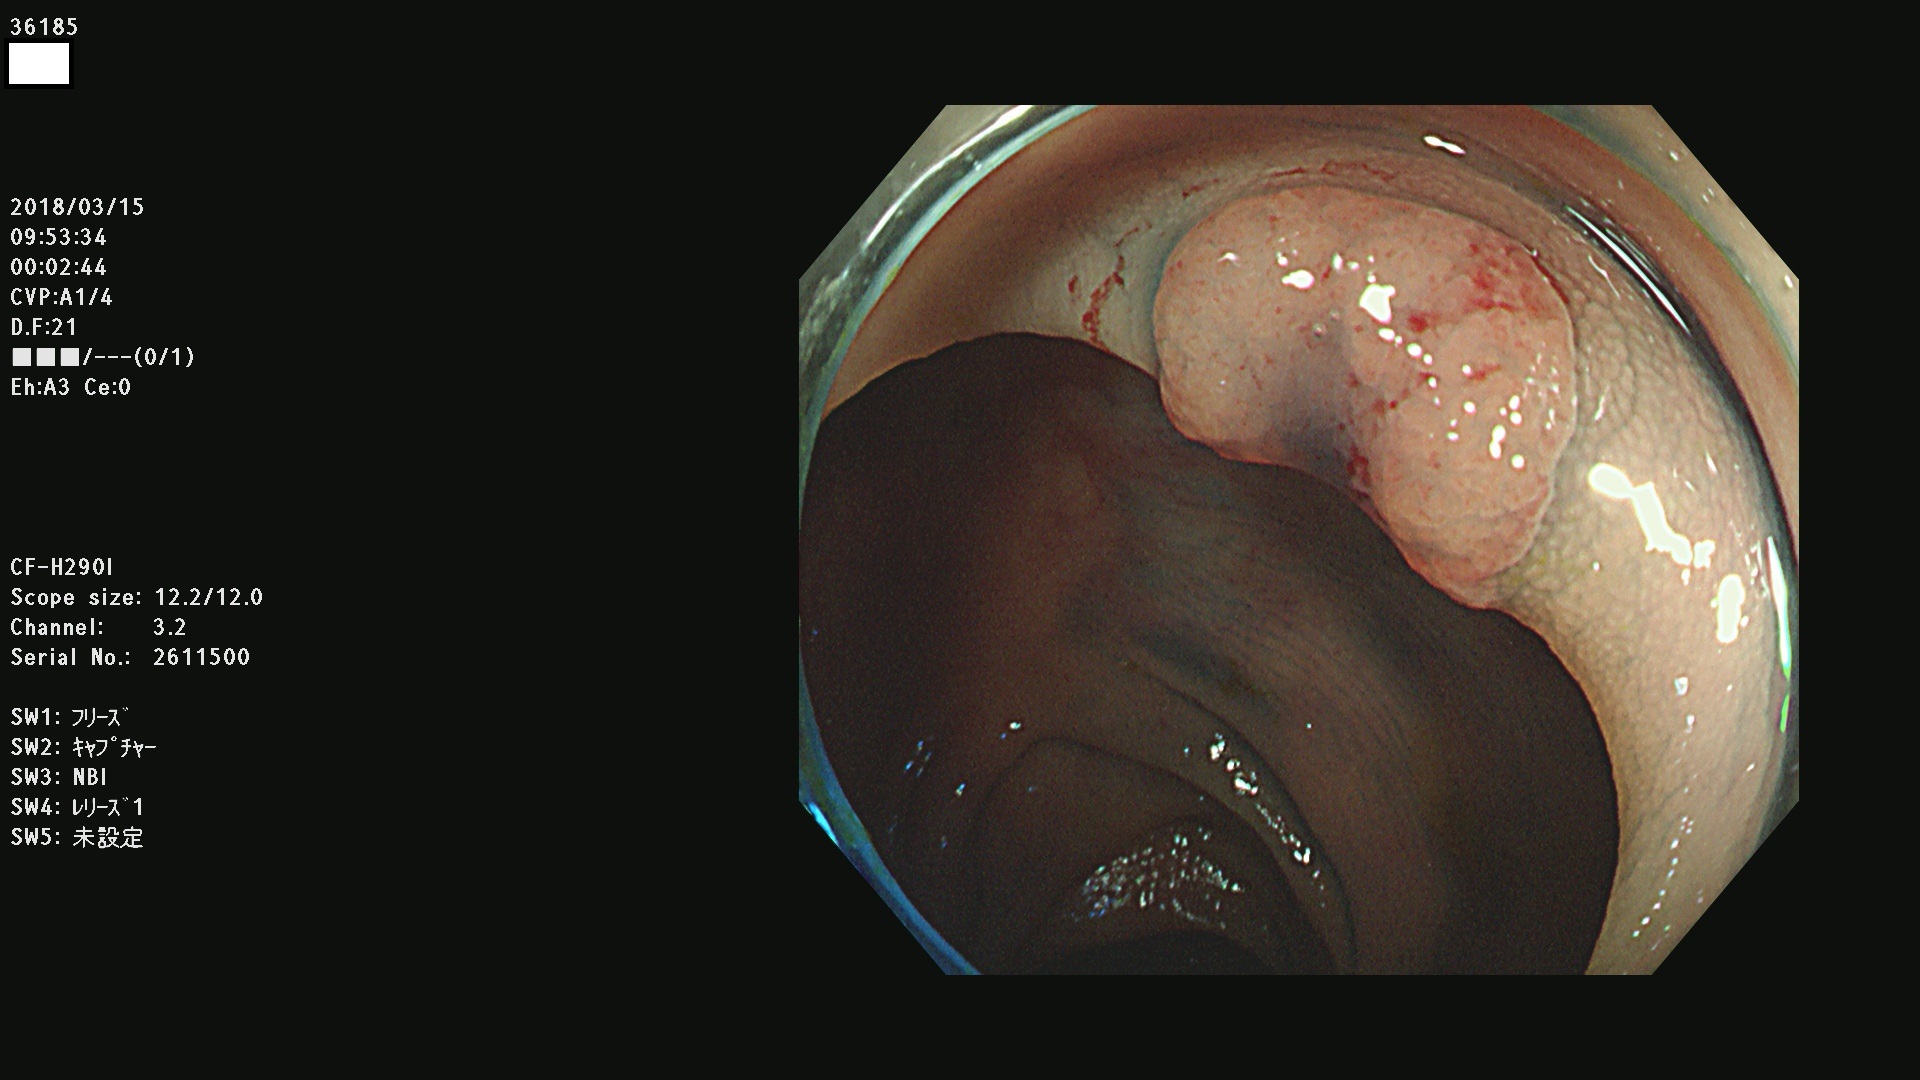

腺腫発見率57 % (カルテ番号 36100〜36199の100名の方の検査結果で集計)大腸癌検診最新情報

以下のカルテ番号の方に腺腫(Adenoma,Group3〜5)が見つかりました(集計法)

36100 36101 36102 36103 36104 36105 36107 36108 36110 36111 36114 36115 36117 36119 36120 36122 36125 36127 36129(SSA/Pのみ) 36133 36135 36137 36138 36139 36143 36144 36146 36147 36152 36153 36154 36155 36157(SSA/Pのみ) 36158 36162 36163 36165 36167 36169 36170 36173 36174 36176 36177 36178 36179 36180 36183 36185 36187 36189 36190(SSA/Pのみ) 36191 36193 36195(SSA/Pのみ) 36197(SSA/Pのみ) 36199(SSA/Pのみ)

発見困難で危険性の高い平坦型病変(上記100名より抽出) ![]()